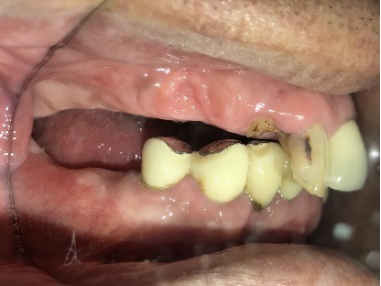

右下のブリッジがゆらゆら動く。

ブリッジの支台になっている奥の歯が、被せ物の中で虫歯になり、支台の役割を果たさず、前方の歯のみで支えられていました。前方の歯をそのままにして、後方の部分を切り離すと、そのまま取れてきました。中は、虫歯で歯根しか残っていない状況でした。この歯は、根管治療後、単独でオールセラミック冠を被せ、歯のないところにインプラントを埋入しました。

冠の中で大きな虫歯になり支台の役割を果たしていませんでした。

冠はブリッジを切断しただけで取れてきました。軟化象牙質を取り除いたところ、歯根しか残っていない状況で保存できるかどうかのぎりぎりのところでした。